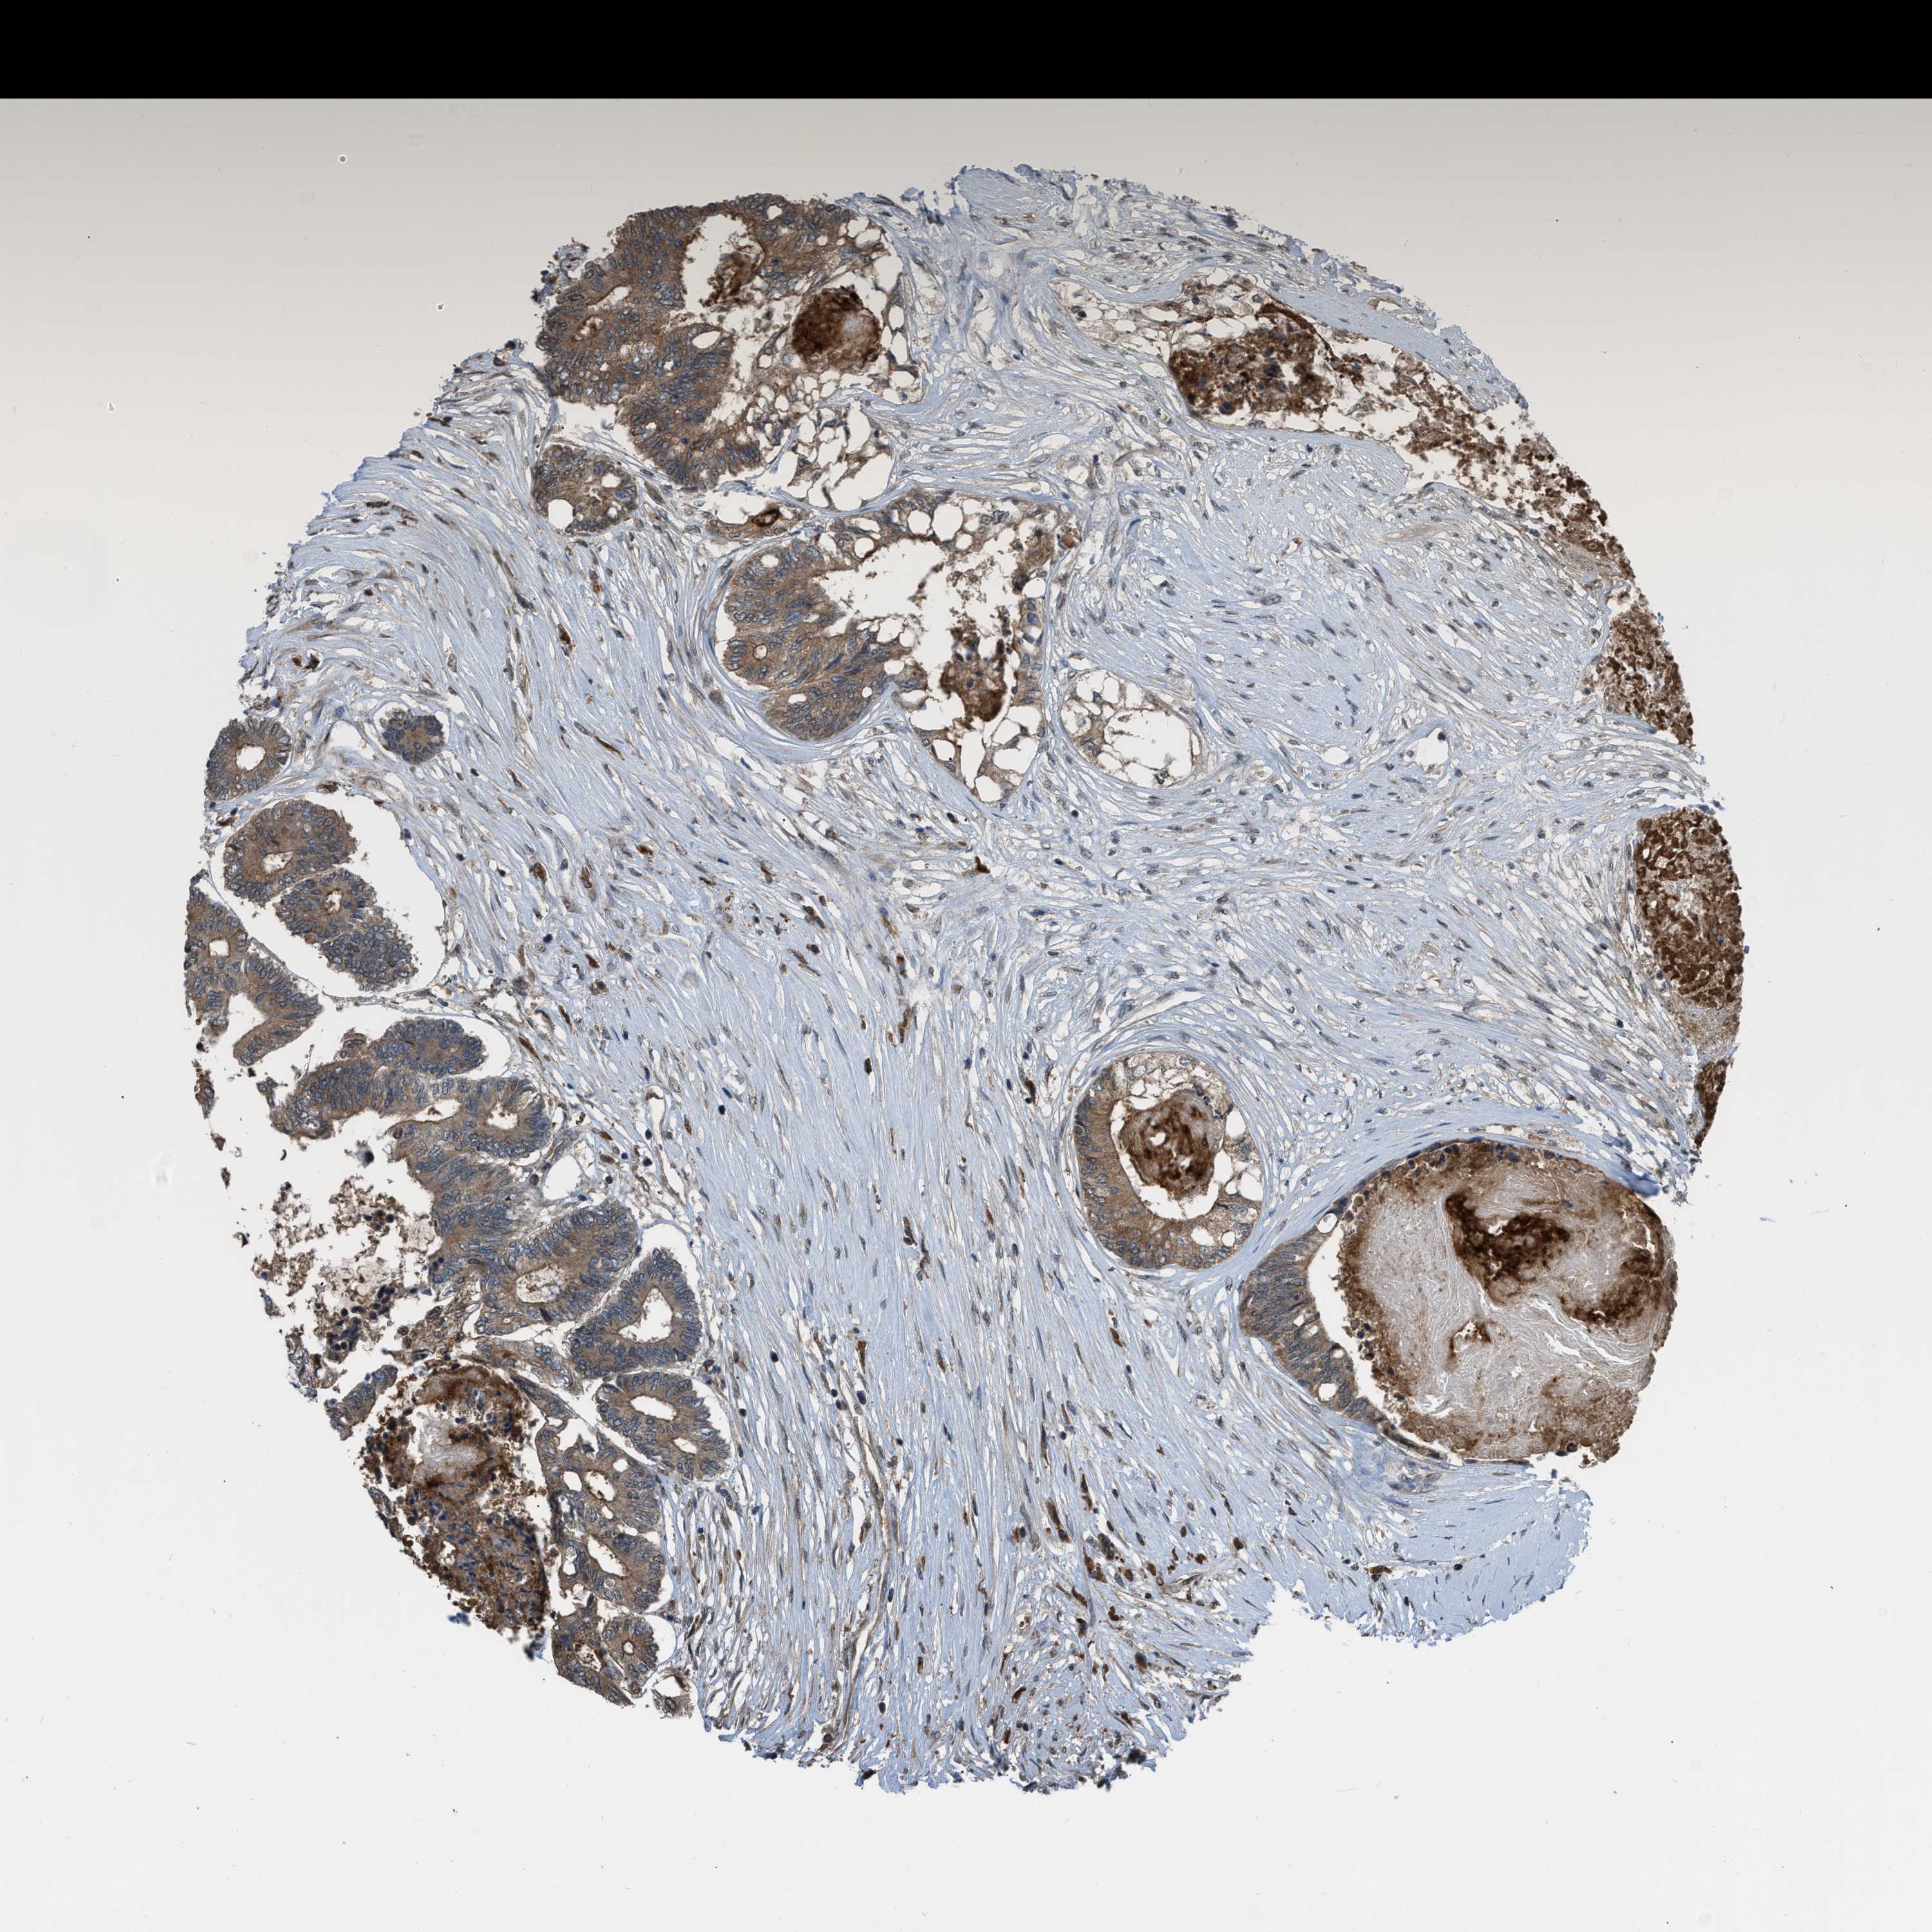

CANCER COLORECTAL CANCER Show tissue menu

Colorectal cancer

Human cancer

Colon adenocarcinoma

Rectum adenocarcinoma